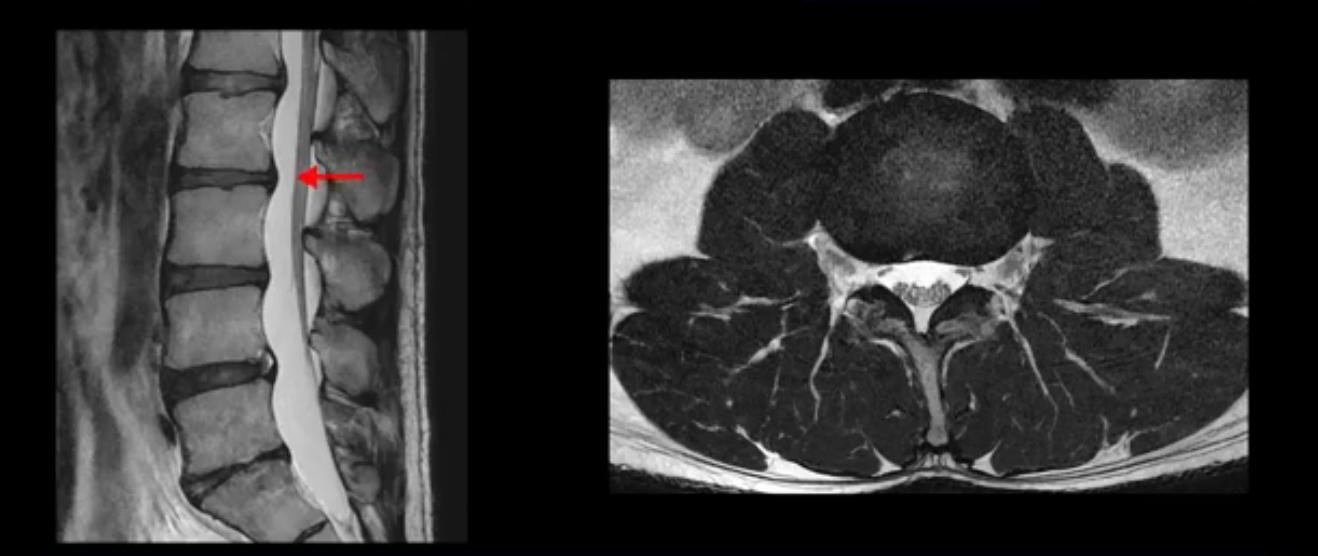

2번 3번도 비교적 디스크 상태는 좋고 신경 구멍 넓이도 아주 넓습니다.

3번 4번도 마찬가지로 디스크상태 좋아 보이고 신경 눌림 전혀 없어 보입니다.